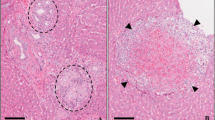

Histopathological changes

We examined histopathological changes in the liver and kidney of the control and treated groups (Table 3, Supple 4). Dose-related histopathological lesions were observed in the liver and kidney of the mice treated with 6 mg/kg AlNPs.

Also, AlNPs injected through the peritoneum in a single acute doses (3.9, 6.4, and 8.5 g/kg) showed the highest accumulation in the spleen followed by the kidney, brain, intestine, and liver, whereas AlNPs injected at a sublethal dose (1.3 g/kg) once in 2 days for 28 days showed the highest accumulation in the liver followed by the spleen, intestine, kidney, and brain (Morsy et al. 2013a, b). Additionally, sphere-type AlNPs (15, 30, and 60 mg/kg), which are administered orally for 4 weeks, accumulated in the brain, thymus, and lung accompanying release from liver (Park et al. 2011). In this study, the AlNPs (rod-type) accumulated in the liver (5.9-fold), kidney (3.1-fold), lung (2.9-fold), and heart (2.9-fold) and were released from the brain. Furthermore, the tissue samples examined in the previous study (sphere-type) did not show any histopathological lesions, whereas, in this study, dose-related histopathological lesions were observed in the liver and kidney of the mice treated with 6 mg/kg of AlNPs (rod type). The shape of nanomaterials is as important as size in determining the toxicity of nanoparticles (Almeida et al. 2011; Perry et al. 2011; Tarantola et al. 2011), and the excretion rate of rod-type was markedly lower than that of sphere-type (Sun et al. 2011). Therefore, we believe that an increase in the LDH levels (6 mg/kg) may be attributed to cell membrane damage following the accumulation of AlNPs (Supple 7) and that further studies are required to determine the relationship between the shape of AlNPs and toxicity.